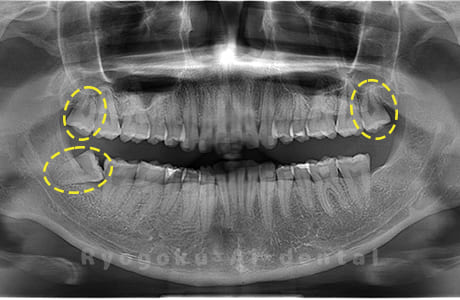

水平埋伏の親知らず

歯茎の中で完全に横に生えてしまうタイプです。

この親知らずを水平埋伏智歯と言います。このタイプはほとんどが下顎のケースです。真横に生えているので抜歯の際は難易度が高く2~3つに砕いて分けて抜歯をします。